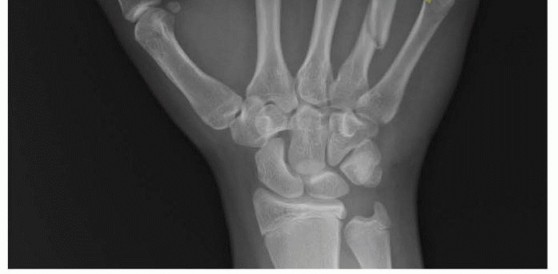

Standard radiographic imaging forms the cornerstone of diagnostic evaluation, requiring, at minimum, a dedicated posteroanterior (PA), a true lateral, and a pronated oblique view of the injured hand. The PA view is excellent for assessing coronal plane angulation and transverse displacement, though it notoriously underestimates sagittal plane deformity. The true lateral view is critical for quantifying apex-dorsal angulation, though overlapping metacarpal shadows can complicate interpretation. The pronated oblique view often provides the clearest visualization of the fracture profile and the degree of comminution.

When standard radiographs are equivocal, or when dealing with complex intra-articular fractures and suspected CMC fracture-dislocations, advanced cross-sectional imaging is mandatory. High-resolution Computed Tomography (CT) with 3D reconstructions provides unparalleled detail of articular step-offs, occult comminution, and the precise spatial orientation of fracture fragments. This information is invaluable for determining the feasibility of lag screw fixation versus the necessity of bridge plating. Furthermore, obtaining radiographs of the uninjured, contralateral hand serves as a vital anatomical template, allowing the surgeon to accurately gauge the patient's native metacarpal length and intrinsic diaphyseal curvature.

Clinical & Radiographic Imaging Archive